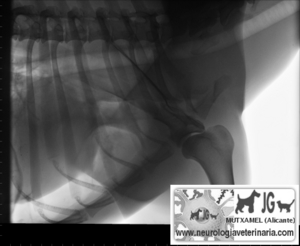

Radiografía del mismo paciente en el momento del accidente (nótese el neumotórax consecuente a la fractura de escápula) |

Nótese la perforación de la caja torácica |

Neumotórax |